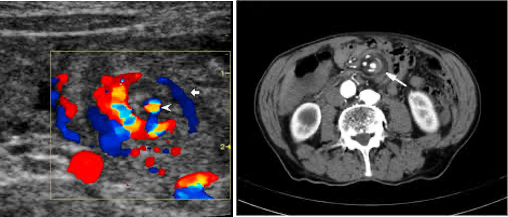

초음파: SMA/SMV 위치 역전

좌: 정상 소견 (V우측, A좌측)

우: malrotation 환아 (A우측, V좌측)

midgut volvulus

whirlpool sign (영상검사 상 sma 주변으로 장간막이 소용돌이 치는 모습)